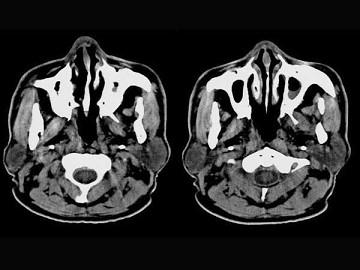

问题 男,61岁,流鼻血三天。如图所示最可能的诊断为 ( )

选项 A、小唾液腺瘤 B、鼻咽部息肉 C、鼻咽腺样体增生 D、鼻咽纤维血管瘤 E、鼻咽淋巴滤泡增生

答案 E